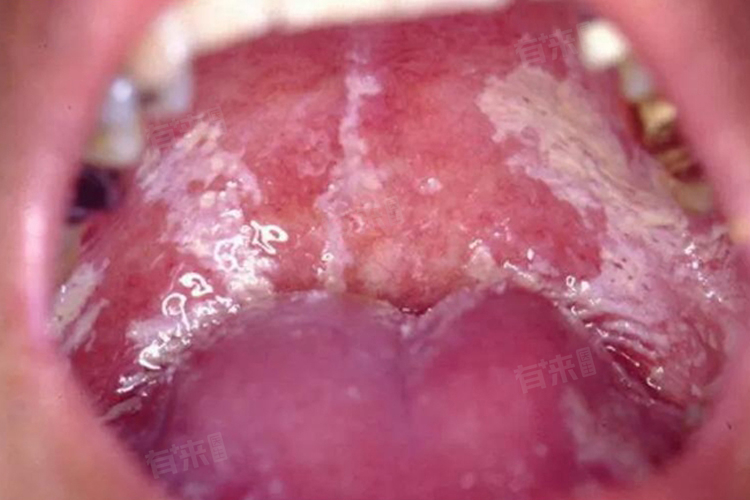

口腔念珠菌病

口腔黏膜表面可出现白色凝乳状的假膜,不易擦去,强行擦去后,下方可见红色的创面,轻微出血。患者可能会感到口腔有烧灼感、干燥感或轻微疼痛,一般不影响进食,但如果病情严重,也可能出现吞咽困难。